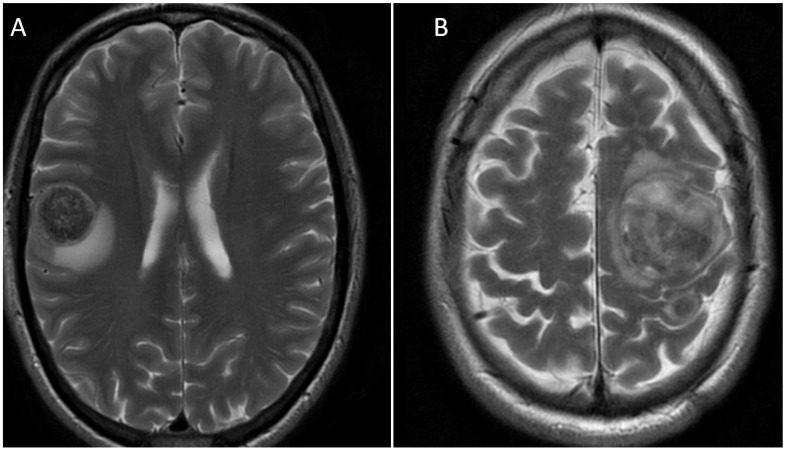

The clinical course and treatments of the patients with brain metastases from GOCs are summarised in Table 2. There is a wide range in overall survival seen in this cohort (range 6–902 days). The patients with the longest survival had minimal extracranial disease with small-volume nodal disease only at time of diagnosis of brain metastases. Both patients (50- and 52-year-old males) presented with brain metastasis from primary gastroesophageal junction tumours, with only local nodal metastasis as their other sites of metastatic disease. Representative images of their initial brain metastases can be seen in Figure 2. This permitted adequate local treatment for the brain metastasis, including surgical metastectomy and post-operative radiotherapy, prior to proceeding to systemic therapies (see Table 2 below for further details). Interestingly, the first site of subsequent relapse in both patients was intracranial. This suggests a reduced intracranial effect of the systemic treatments used. Of the 12 patients, only 5 (41.7%) were able to proceed to systemic treatments following the diagnosis of brain metastasis. This demonstrates the devastating effect that brain metastasis has on functional status.

Figure 2.

Representative magnetic resonance images (T2 weighted, propeller silent sequencing, and sagittal views of the region of interest) of two patients presenting with metastatic GOCs. (A) A 52-year-old male with primary gastroesophageal junction HER2-positive GOC. (B) A 50-year-old male with primary gastroesophageal junction HER2-positive GOCs. Arrows denote position of metastases.